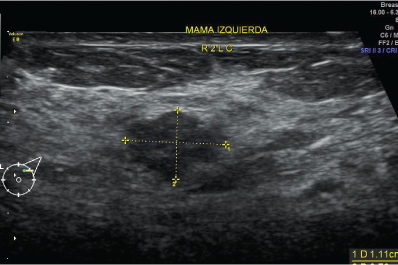

La ecografía mamario utiliza ondas sonoras para producir fotografías de las estructuras internas del seno.

Se utiliza primariamente para ayudar a diagnosticar bultos en el seno u otras anormalidades que su médico podría encontrar durante un examen físico, una mamografía o una RMN del seno.

Sus imágenes pueden ayudar a determinar si un bulto anómalo es sólido, si está llena de líquido o si es a la vez quístico y sólido.